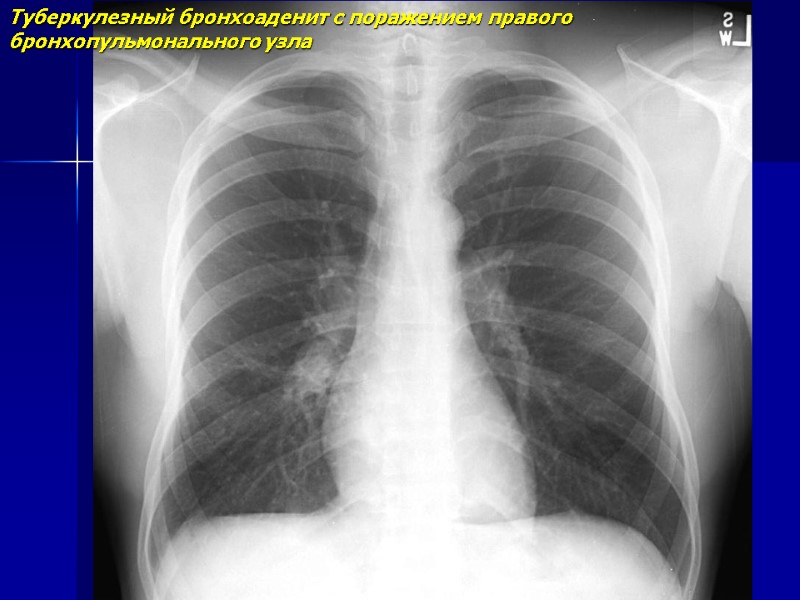

Туберкулезный бронхоаденит с поражением правого бронхопульмонального узла